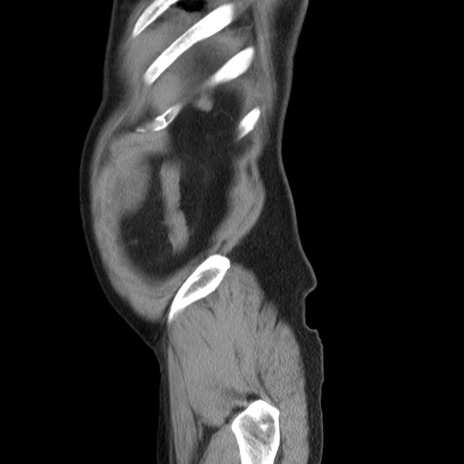

横断像

【症例】 60歳代男性

【主訴】 腹部膨満、嘔吐

【現病歴】5日前頃より倦怠感を認め食事量減少し4日前の朝嘔吐、食事摂取困難となった。 3日前近医受診し点滴施行され整腸剤などを処方された。 当日他院を受診し、腹部膨満著明、炎症反応の上昇(CRP10.8、WBC11200)あり、紹介受診となる。

【身体所見】 意識JCS1 受け答えがはっきりしないBP 111/57mHg、 P 67bpm、、BT35.2°C、SpO2 97%(RA)、 腹部:膨隆、打診で鼓音あり、全体的に圧痛有り、腸蠕動音(-)、反跳痛ははっきりせず。

【データ】WBC 11400、CRP 14.20